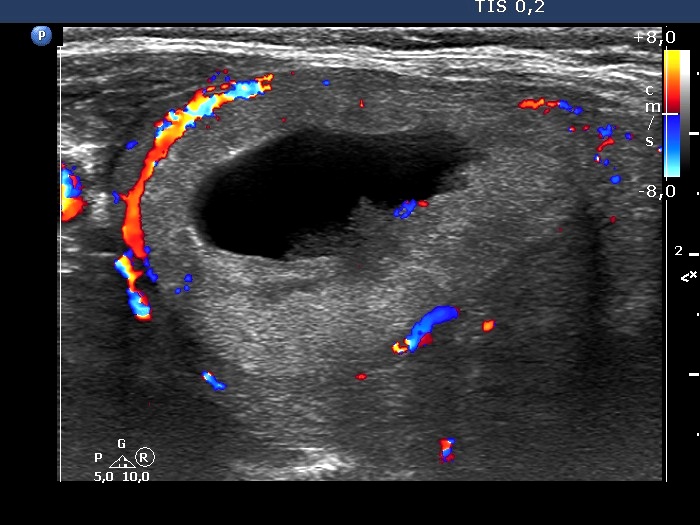

First examination (first row of images):

Ultrasonography. The thyroid was moderately hypoechogenic. There were two central-type cysts, one in the left lobe and another one in the right lobe. Both had perinodular vascularization.4 mL serous fluid was aspirated. Aspiration cytology resulted in benign cystic lesion.

Suggestion: yearly TSH-determination, ultrasound in three years.